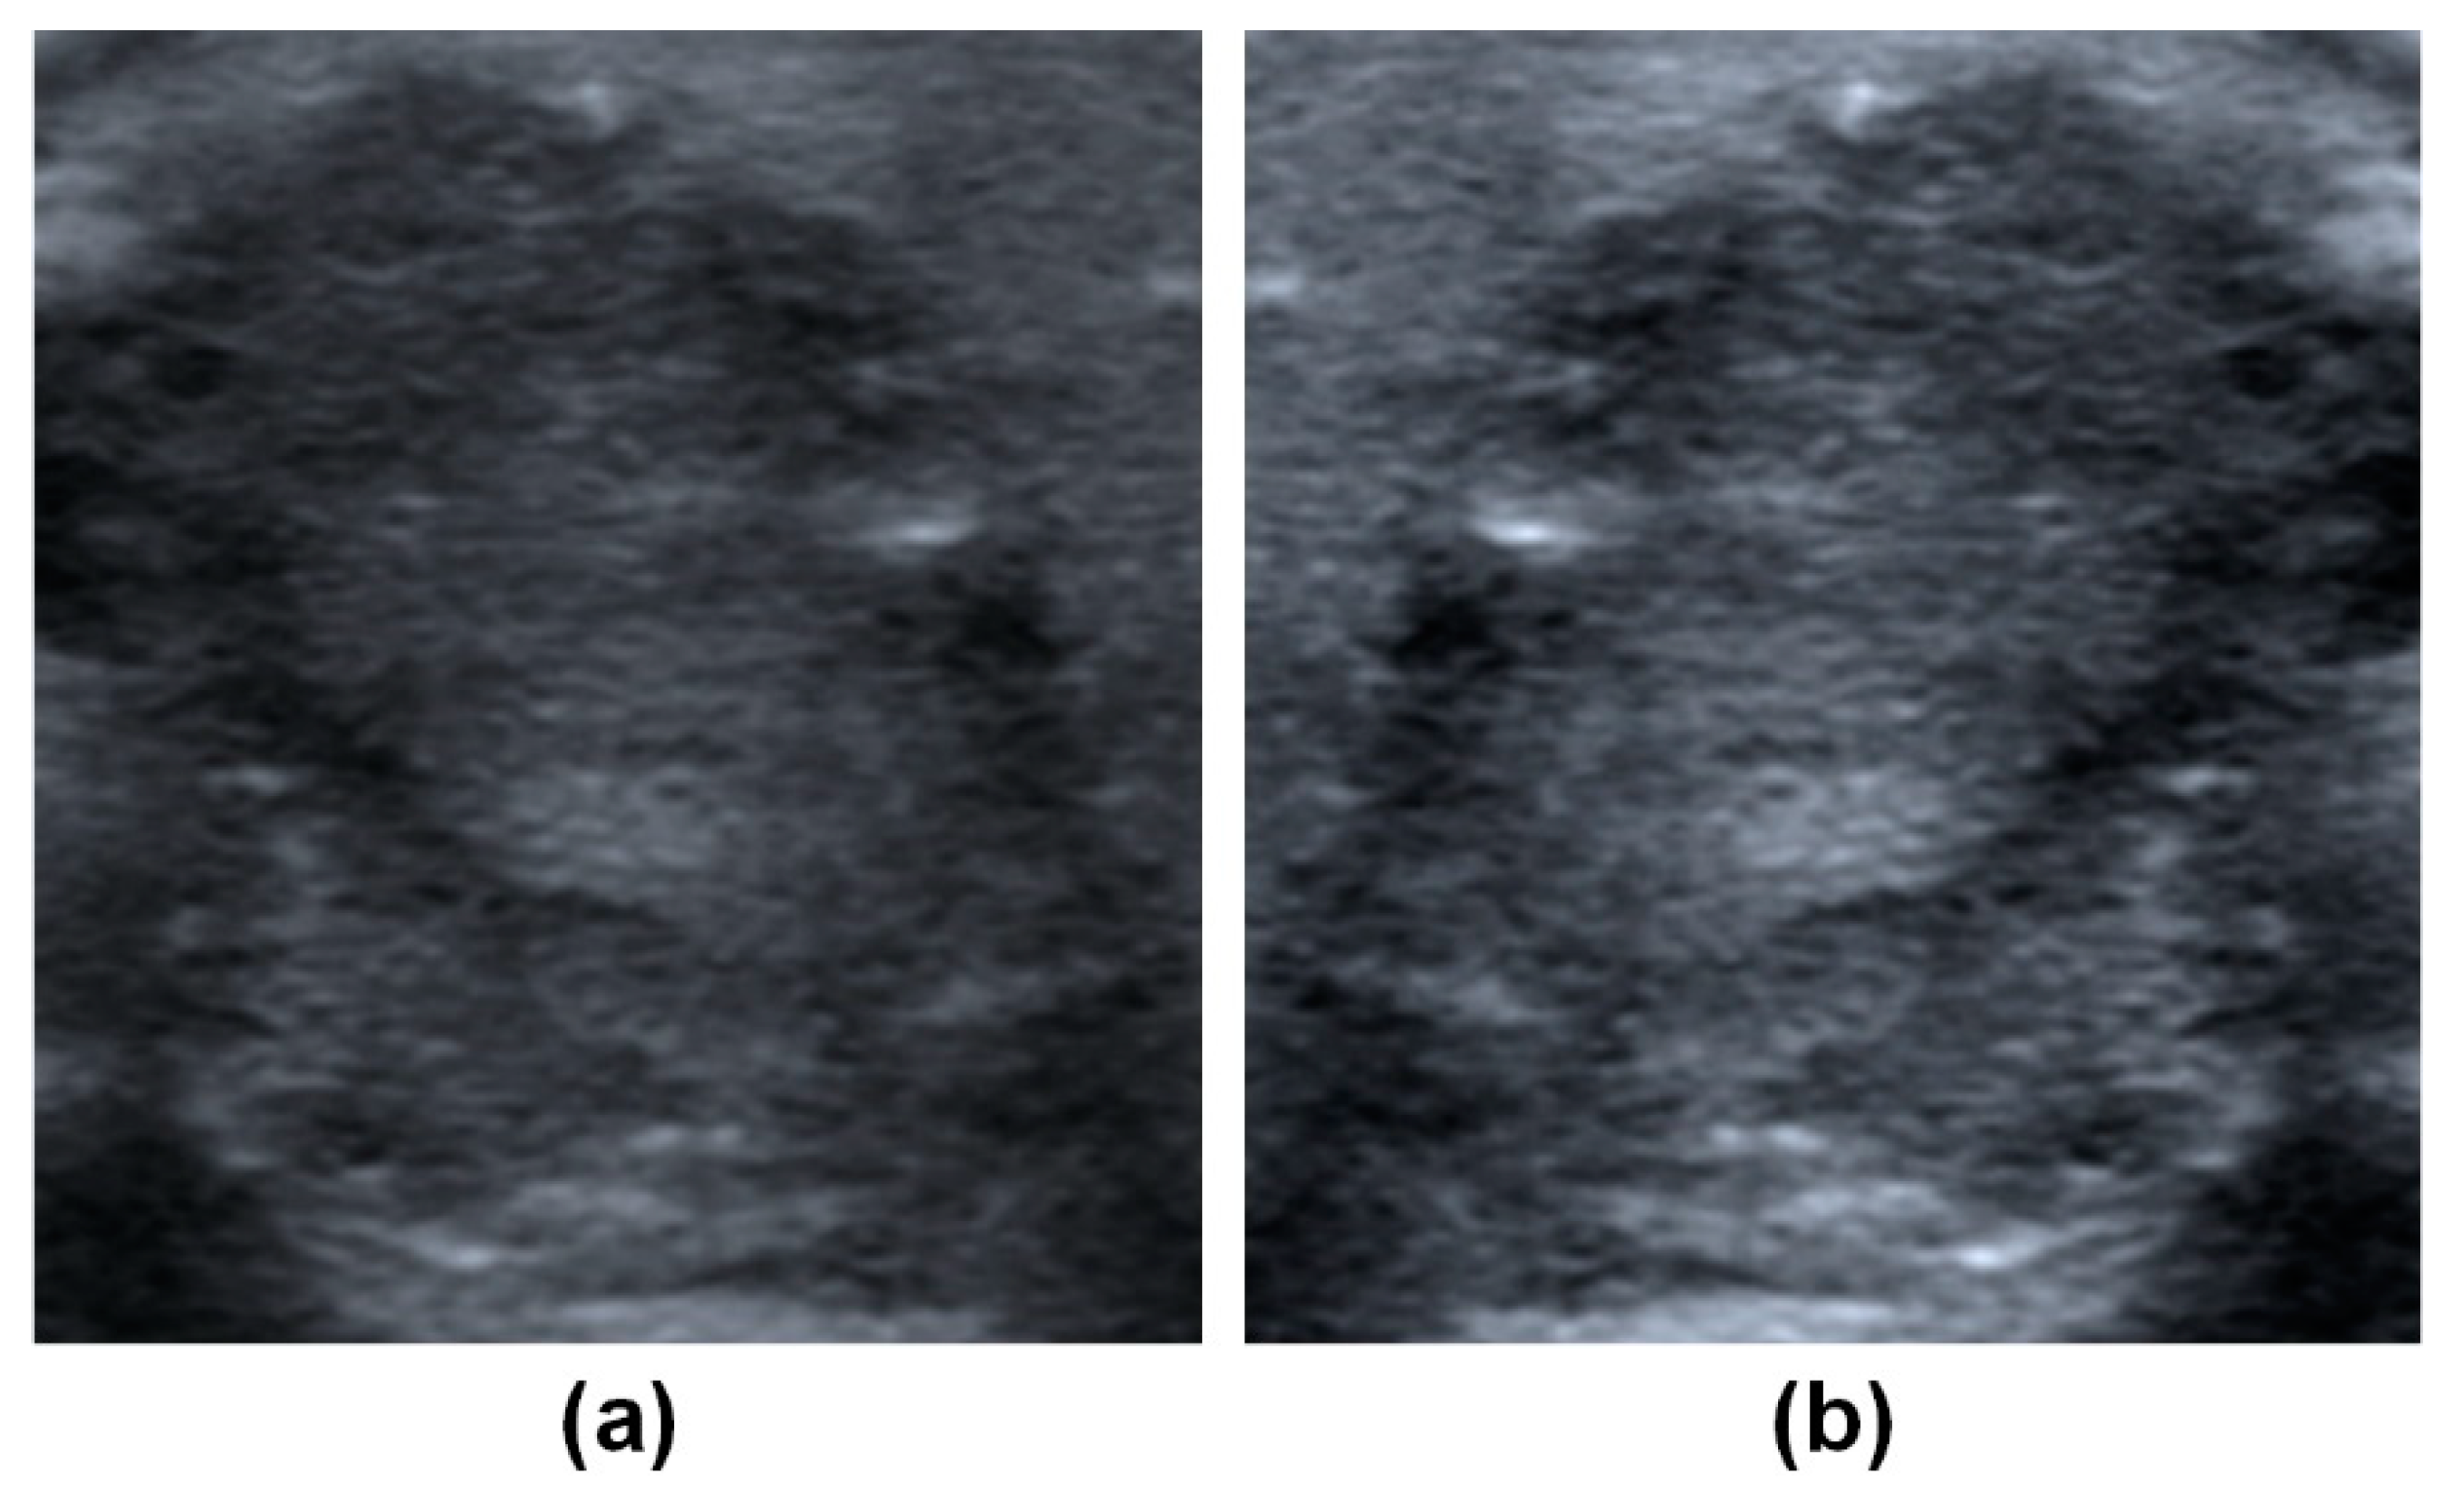

Using Deep Convolutional Neural Networks for Enhanced Ultrasonographic Image Diagnosis of Differentiated Thyroid Cancer

2. Materials and Methods

2.2. Data Collection